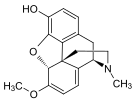

Opium alkaloids

Structures

| Morphides | ||||

Codeine Codeine |

Morphine Morphine |

Oripavine Oripavine |

Pseudomorphine Pseudomorphine |

Thebaine Thebaine |